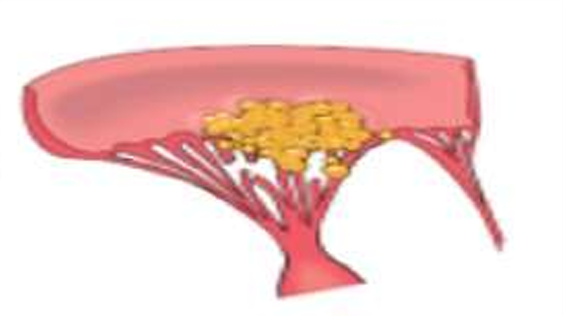

The vegetations of BE consist of 3 zones:

i) Outer cap consists of eosinophilic material composed of fibrin and platelets.

ii) Middle basophilic zone containing colonies of bacteria.

iii) Deeper zone consists of non-specific inflammatory reaction in the cusp itself